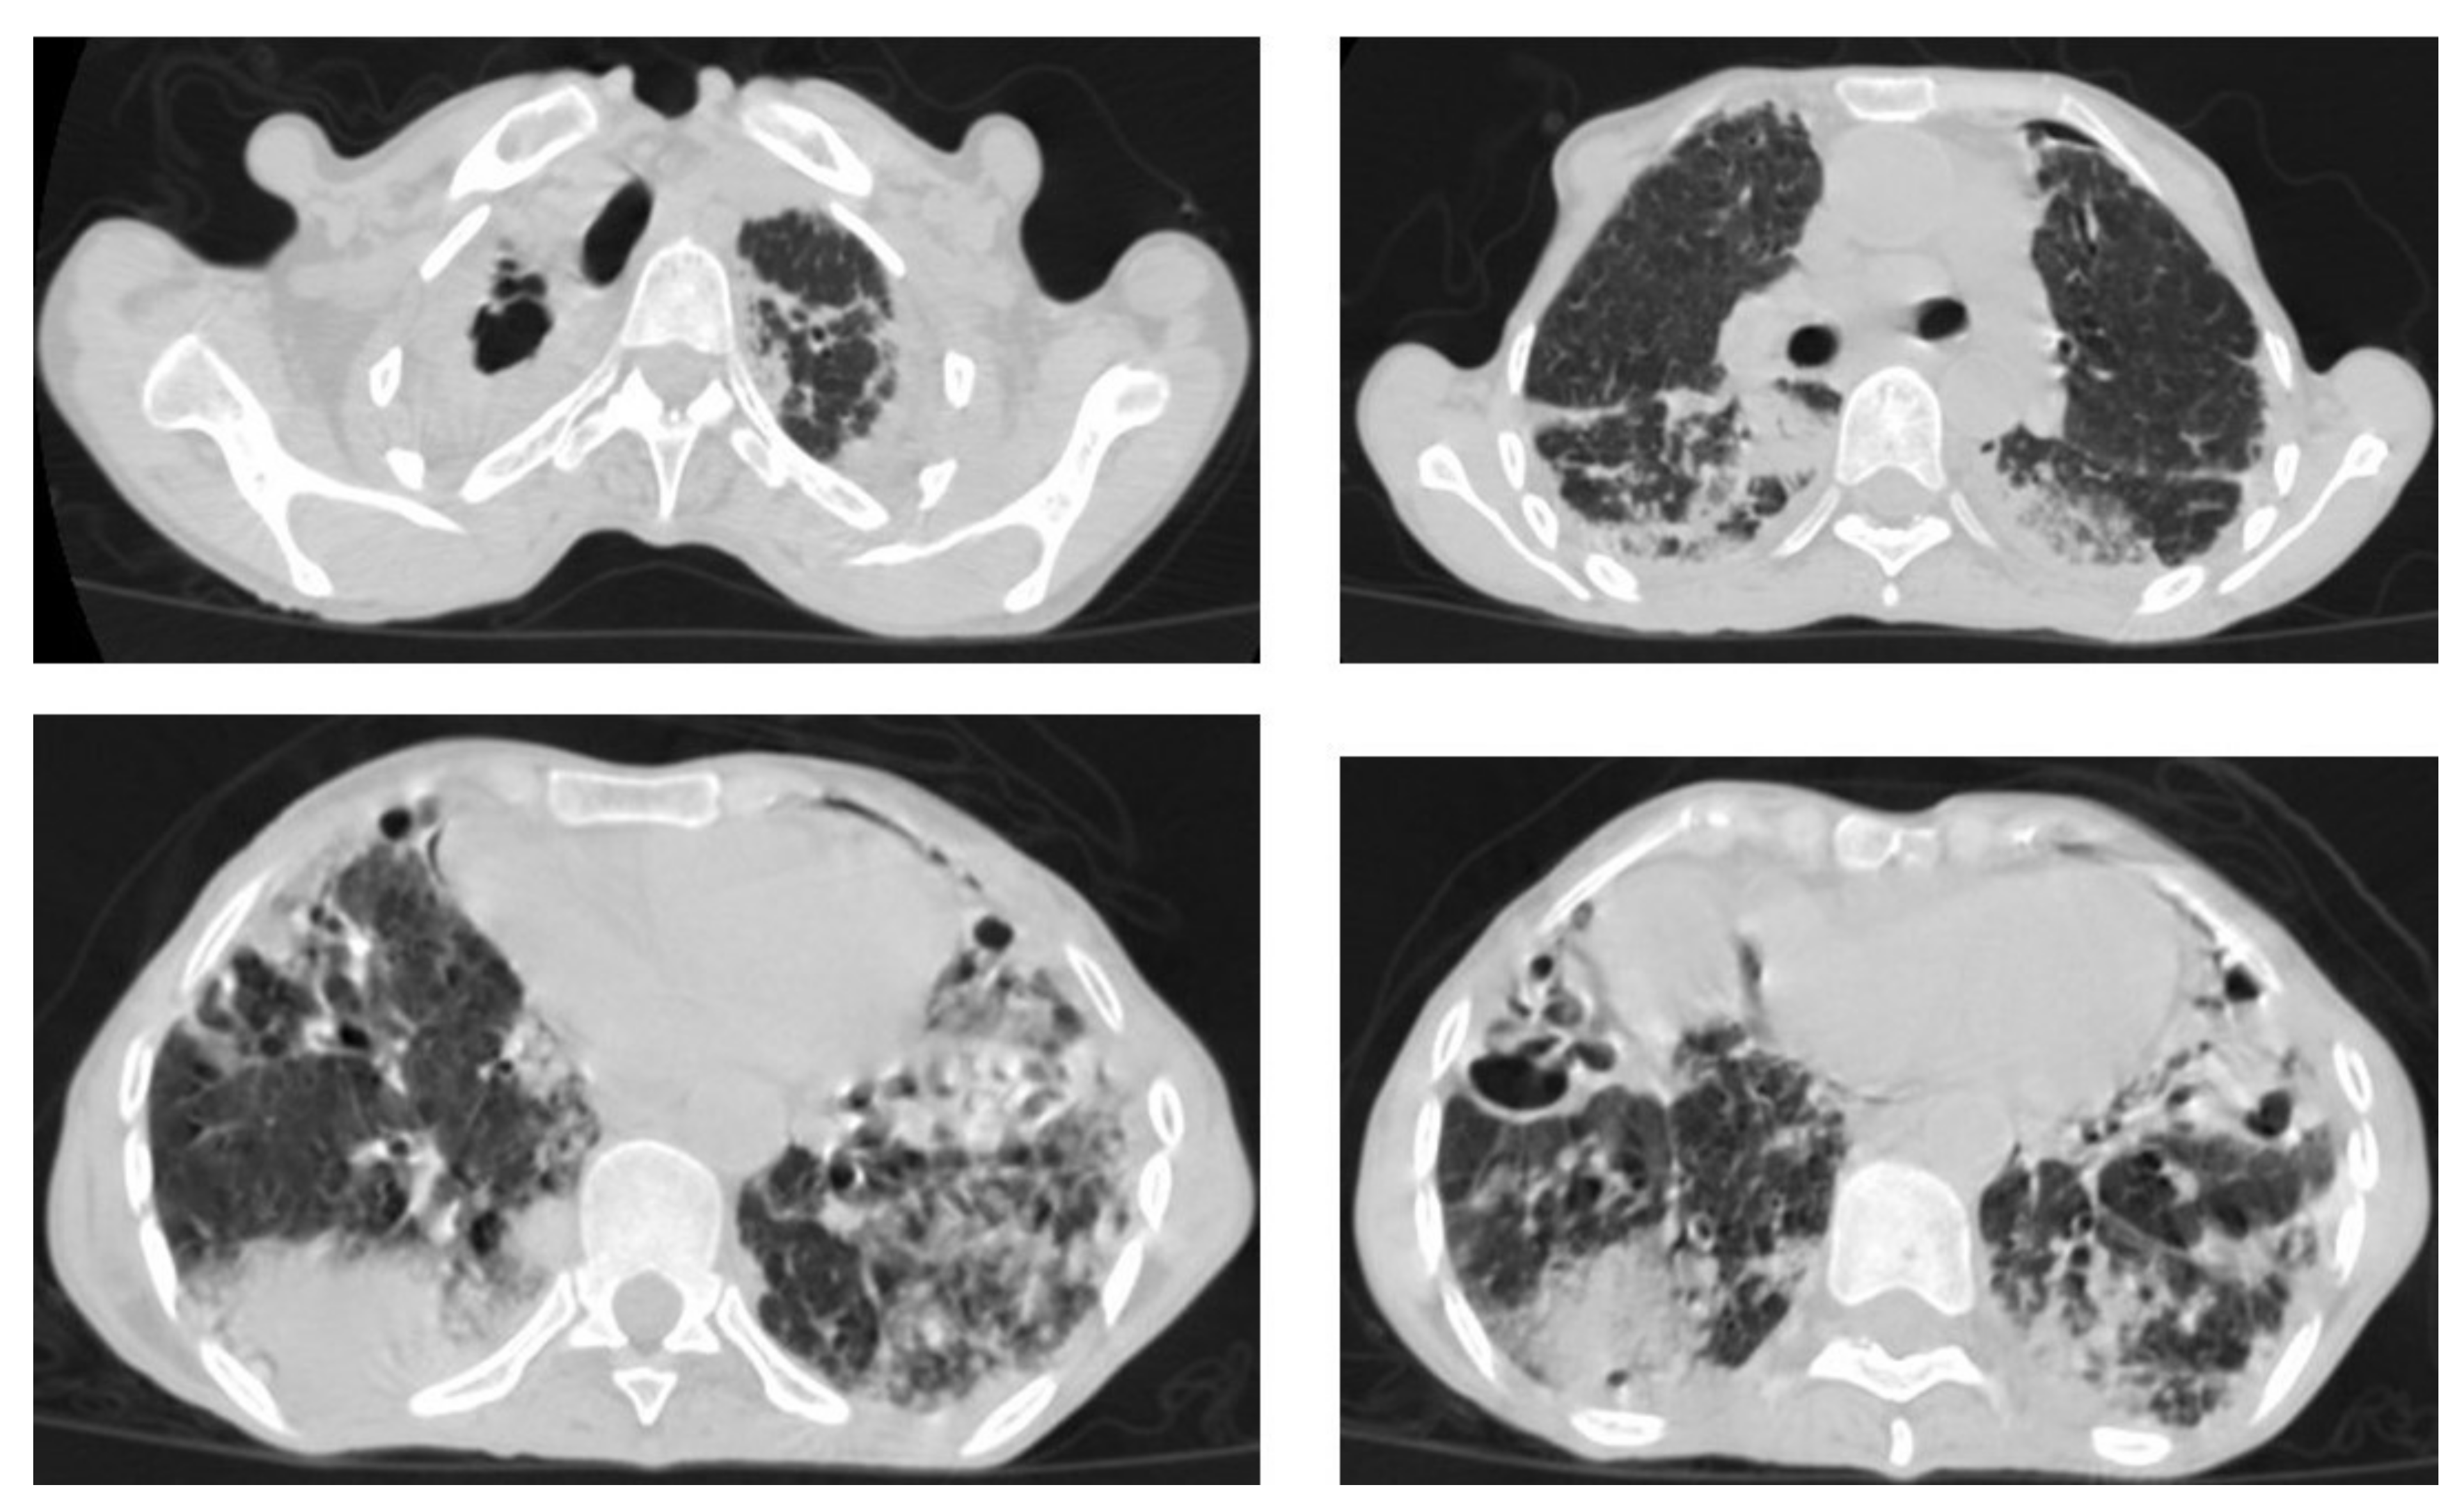

Figure 9. Old reactive TB with superimposed infection in a 75-year-old female with chronic cough and no history of previous medication. Selected axial images of lung CT show prominent fibrotic changes with scarring traction bronchiectasis and decreased volume in the apical and posterior segment of the upper lobes and architectural distortion of the lung parenchyma caused by cystic bronchiectasis predominantly involve bilateral lower lobes, ligula, and right middle lobe. Patchy consolidative areas and ground glass opacities are signs of active infection.

Figure 10. Reactivation of TB in an adult man with chronic cough. Selected axial images of lung CT show cystic bronchiectasis, due to old infection, with peribronchial thickening and air fluid level involving both lower lobes. Scattered tree in bud pattern and infected cystic bronchiectasis indicate active TB.

Even after full treatment of pulmonary TB, complications and residual changes may affect quality of life; these complications can be misinterpreted as other active diseases, causing diagnostic pitfalls. TB complications in the lung parenchyma include tuberculoma, thin-walled cavities, cicatrisation collapse (Figure 9), and lung cancer, although this is rare. Complications in the airway include bronchiectasis (Figure 10) and tracheobronchial stenosis. Extrapulmonary complications include pleural thickening and calcification, fibrothorax, bronchopleural fistula, and pneumothorax (Figure 11). Vascular complications include Rasmussen aneurysm, calcified mediastinal lymph nodes, fibrosing mediastinitis, and constrictive pericarditis [23].